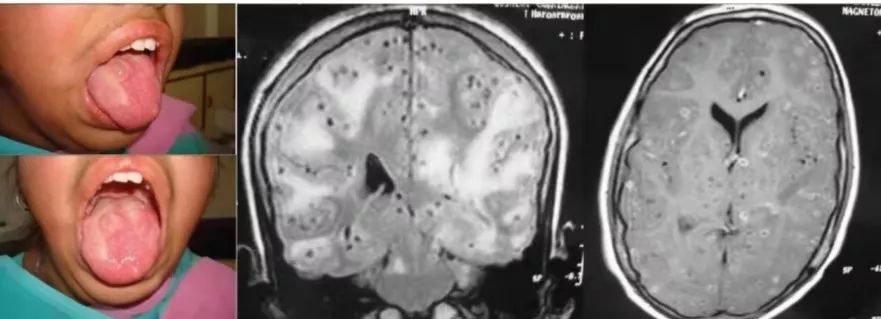

14岁的女孩,舌部有多处软肿。认知能力下降,出现了躁动症。精神运动迟钝,领会成绩下降。MMSE评分为22/30。

答案:脑囊虫病。

患者的舌体显示多发性囊性结节性肿物,触诊边缘不清的软结节,无压痛。核磁共振显示多发性肉芽肿,提示脑囊虫病的不同时期。少数肉芽肿也显示出偏心的头节。组织病理学检查显示囊虫病幼虫的导管样内陷,由均质膜衬里的幼虫组成。脑实质型脑囊虫病MRI较有特征,多为圆形囊性病变,2-8mm大小,其内可见偏心的附壁小点状影,代表囊虫头节。脑囊虫存活期水肿轻。增强扫描囊壁可强化或不强化。囊虫死亡时,头节显示不清,周围水肿加剧,占位明显,强化环厚度增加。此时可见“白靶征”,即T2WI囊液及周围水肿呈高信号,而囊壁与囊内模糊不清的头节呈低信号,低信号为囊虫逐渐纤维化、机化和钙化,含水量减少,氢质子密度减低所致。